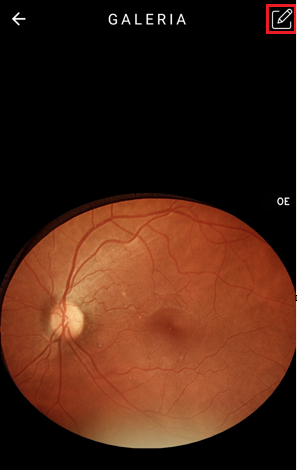

- Opção de medição CDR (CUP TO DISC RATIO), encontre a razão entre o nervo óptico e a escavação, detectando alterações glaucomatosas pela espessura da área de rima.

Clique em cima da imagem que deseja editar, ela ampliará, e após, no ícone . Selecione a opção de edição “CDR”.

Olhos normais obedecem a regra Inferior ≥ Superior ≥ Nasal ≥ Temporal

Mais espesso na região Inferior e mais fino na região Temporal

Junto com a opção CDR na tela de edição, será demonstrado em um gráfico dinâmico com as variações das espessuras medido em micrômetros (µm).